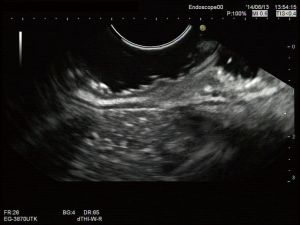

Early stage gastric cancer patients are fit for totally laparoscopic uncut Roux-en-Y gastrojejunostomy after distal gastrectomy. In the present video (Figure 1), the patient is a 61 years old woman who was diagnosed moderately differentiated adenocarcinoma of antrum by gastroscopy and histological test (Figure 2). The tumor stage was assessed to be cT1N0M0 by CT scan preoperation and EUS (Figures 3,4).